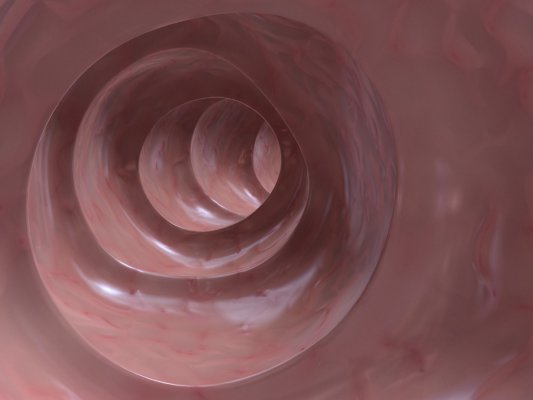

Syöpä 10.11.2020 12:42 VIRPI EKHOLM INGIMAGE